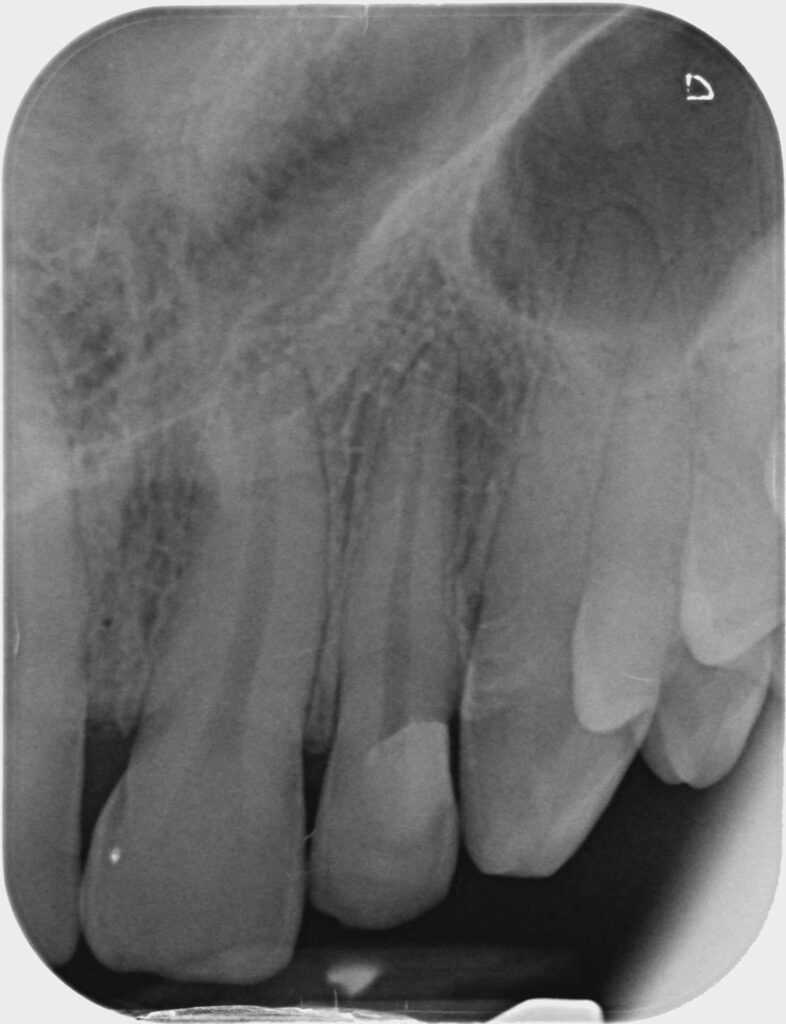

Rimossa la diga, si procede con la lucidatura del complesso restauro-dente mediante frese carborundum e gommini di durezza decrescente. Viene eseguita la radiografia intraoperatoria a lembo aperto (Figura 6).